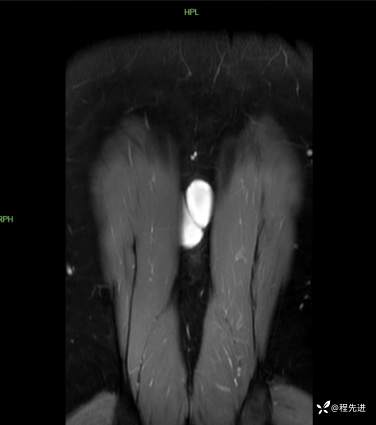

T1增强压脂冠状位:

T2横断位: